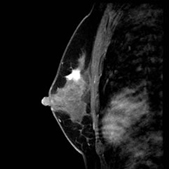

画像中偏上处白色不则部分为癌(治疗前)

治疗6个月后,白色部分变小

治疗一年后白色部分有明显缩小的变化